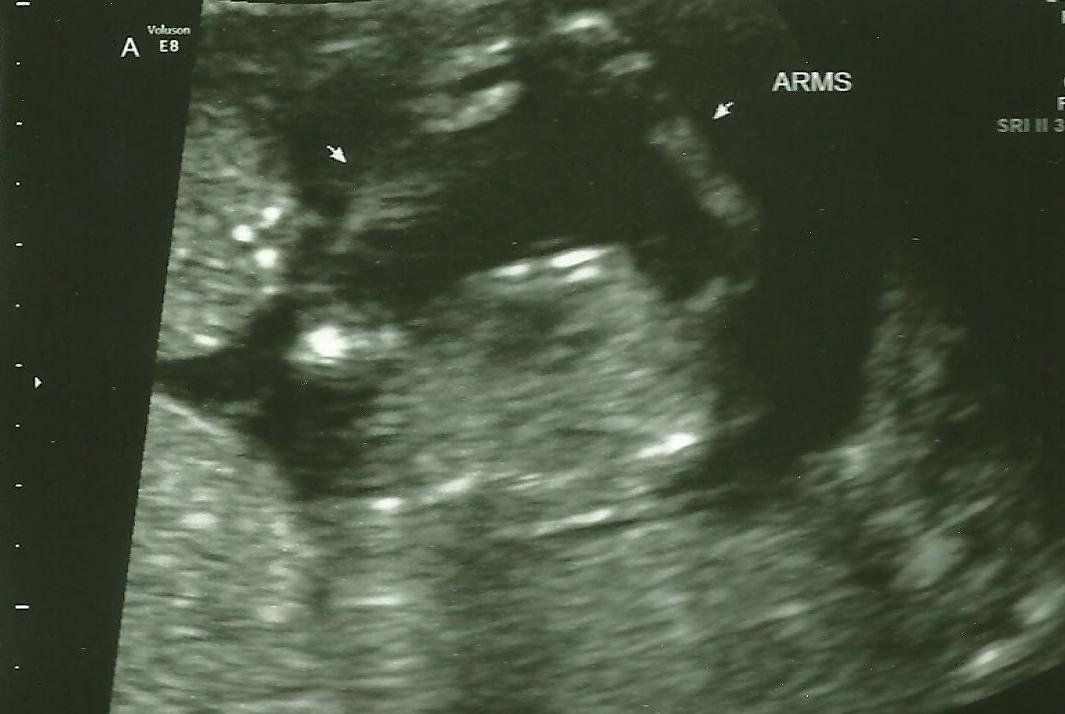

Arms:

(It is a view from the bottom looking up towards its head. Sort of like looking at the underside of a hug.)